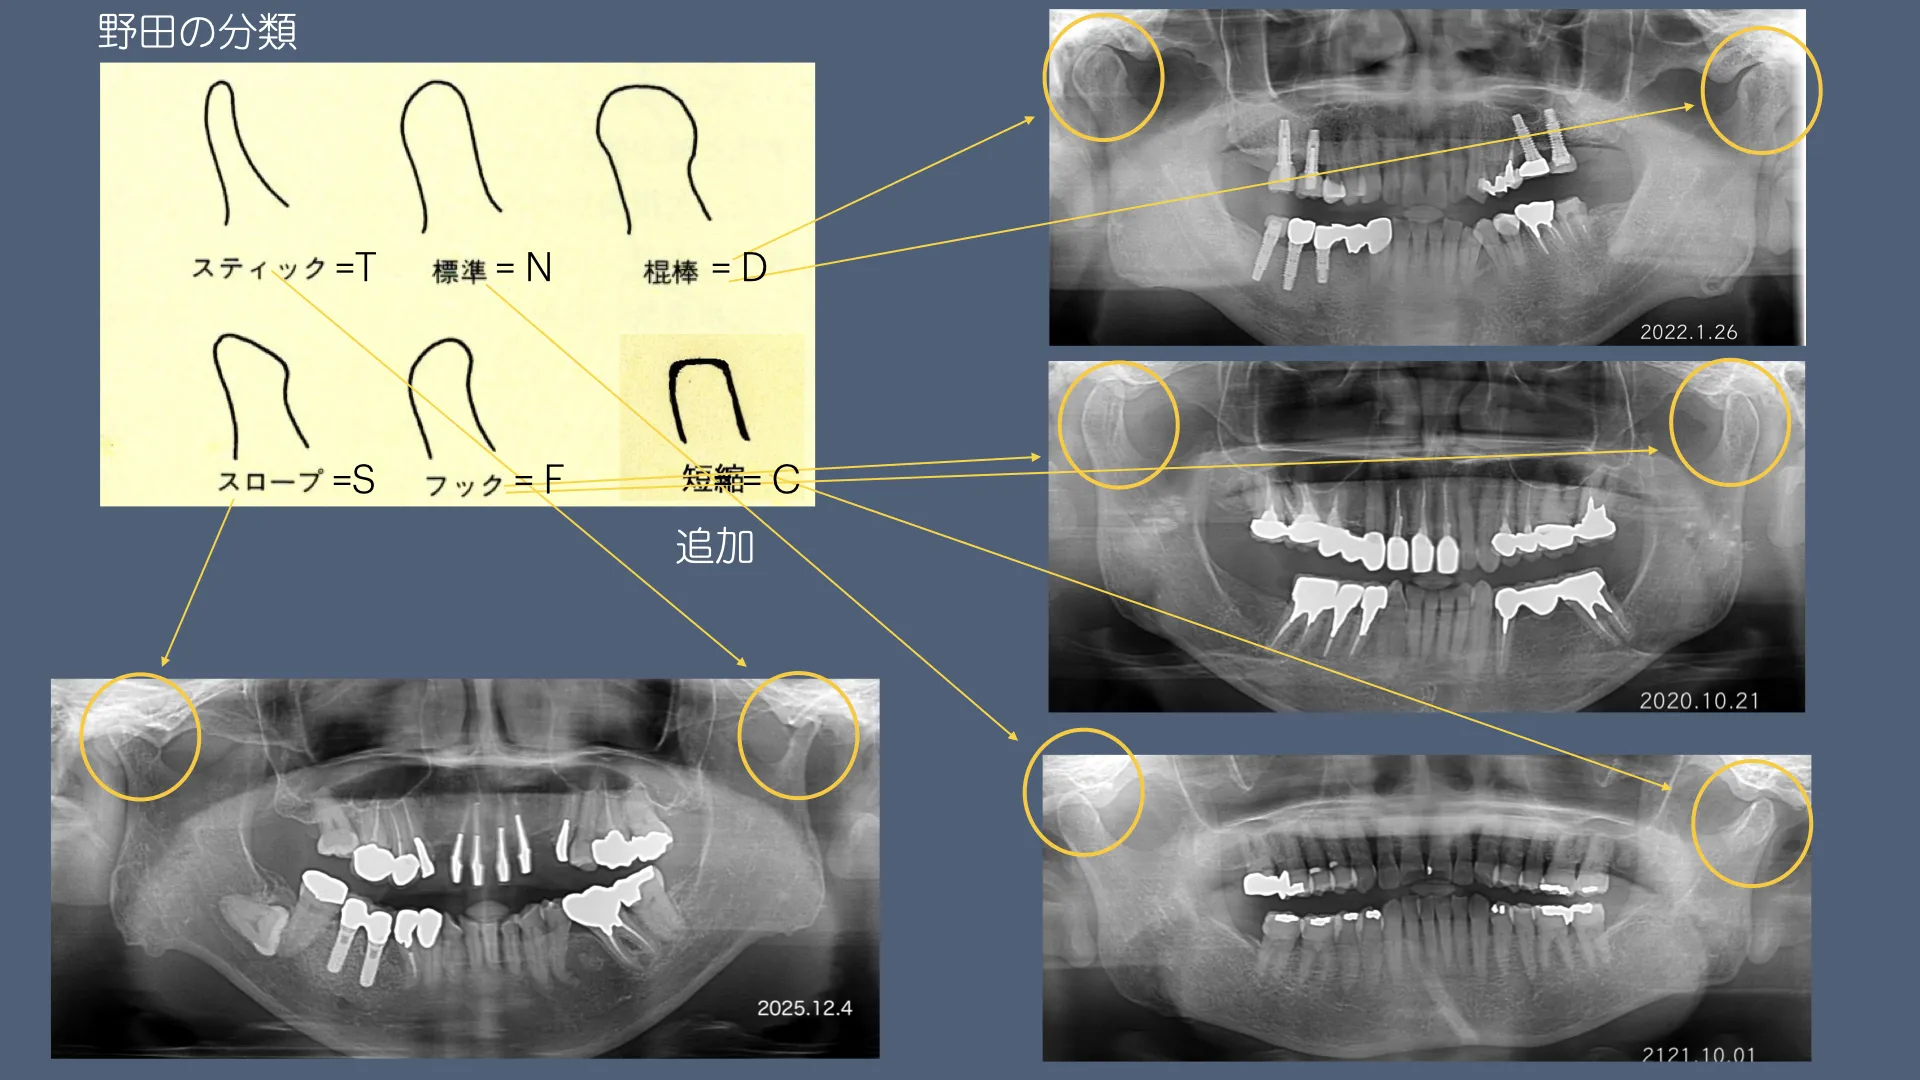

昨日はスタディグループ火曜会での発表の当番でした。今回も顎関節症関連のテーマで行いました。タイトルは『パノラマX線写真での顆頭形態の考察ー顆頭形態の多様性とその左右差及びリモデリングについて』です。この発表をまとめるために倉庫に籠り、昔のレントゲン写真を探したりして患者さんの顎関節の変化を確認しました。やはり改めてしらべてみると新たは発見があり勉強になりました。